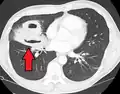

Pulmonary abscess on CT scan -

A subpleural abscess.